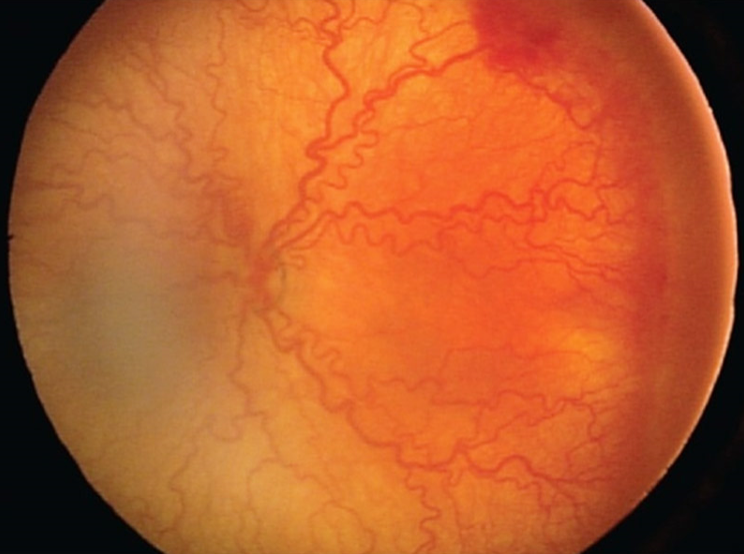

미숙아망막병증은 망막혈관의 이상으로 미숙아에서 발생하는 질환으로 소아 실명의 가장 중요한 원인을 차지하고 있습니다. 최근 의학의 발전과 더불어 미숙아의 생존율이 높아지면서 미숙아망막병증의 발생률도 증가하고 있습니다.

이른 출생으로 인해 자궁 내의 환경보다 상대적으로 산소 분압이 높은 고산소환경과 모체로부터 전달되는 혈관형성인자의 결핍이 원인입니다. 전체 미숙아 중 약 20~30% 내외에서 발생하며, 자연경과 중 대부분 저절로 퇴행하고 6% 정도에서만 치료가 필요한 심한 망막병증으로 진행합니다. 이 경우 신생혈관이 증식하고 종래에는 견인망막박리가 발생할 수 있습니다.

미숙아망막병증이 진행하면 치료를 고려하게 됩니다. 레이저치료, 안구내 약물주사 등이 시도되며 망막박리가 발생한 경우 수술이 필요하나 시력 예후가 좋지 않다고 알려져 있습니다.